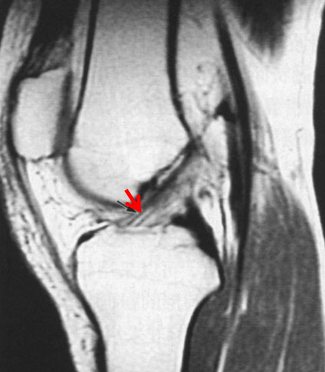

MRI

正常前交叉韧带

前交叉韧带损伤后形成的疤痕组织